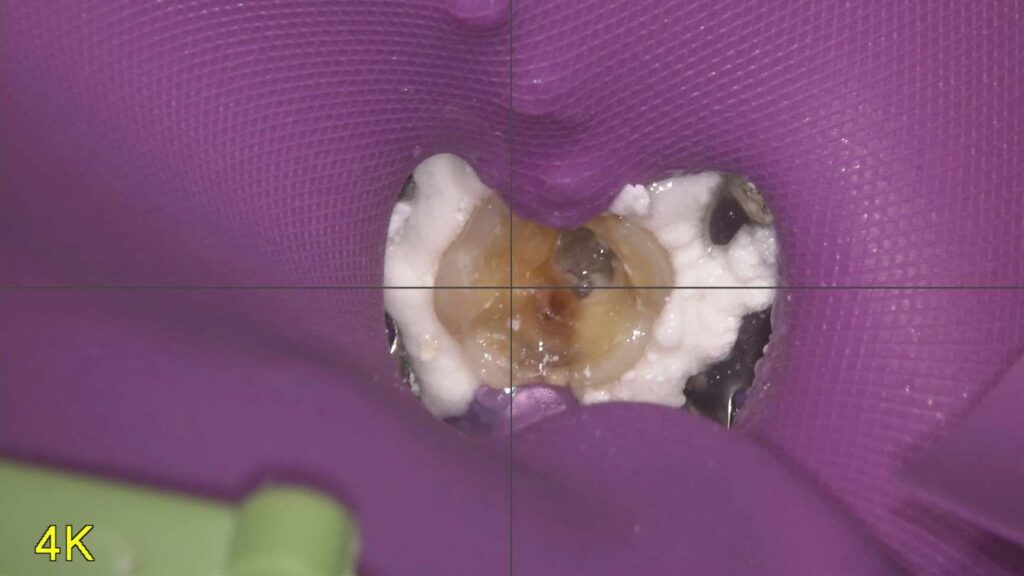

【当院のこだわり】根管治療ではラバーダムを使用します

歯の神経の治療(根管治療)は、むし歯治療の中でも特に繊細で清潔さが求められる処置です。その成功率を高めるために、当院で…